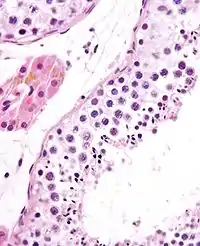

Tub seminifer conţinând spermatozoizi maturizați

În biologie, spermatogeneza reprezintă procesul de formare a spermatozoizilor. Se desfășoară în tuburile seminifere, în trei zone distincte ale acestora, corespunzător celor trei perioade ale spermatogenezei:

- perioada de maturație: spermatocitele primare se divid de două ori consecutiv și din fiecare rezultă patru celule (spermatide), care, după unele transformări, devin spermatozoizi.